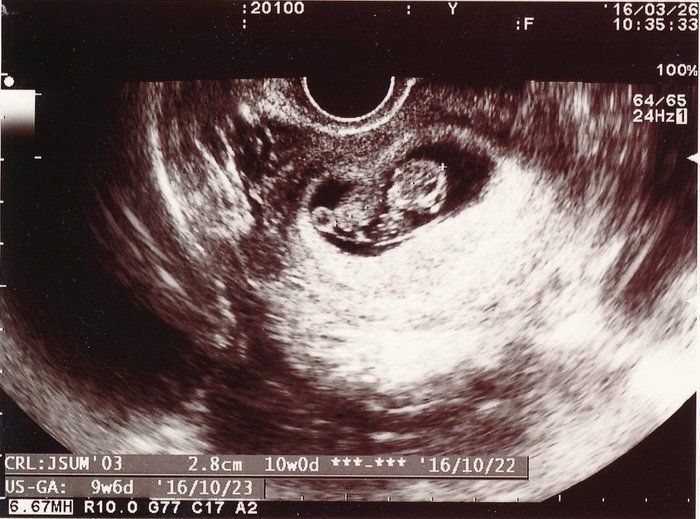

小吉さんの妊娠9週目のエコー写真

赤ちゃんは2.8cmになりました。ハート型のように写っている胎嚢の右側にあるのが頭で左側が体です。人間らしくなってきたのが嬉しかったのを覚えています。マクロビオティックの先生からいただいたアドバイスを元に、食事内容や体を冷やさないことなどに注意をしながら慎重に毎日を過ごしていました。